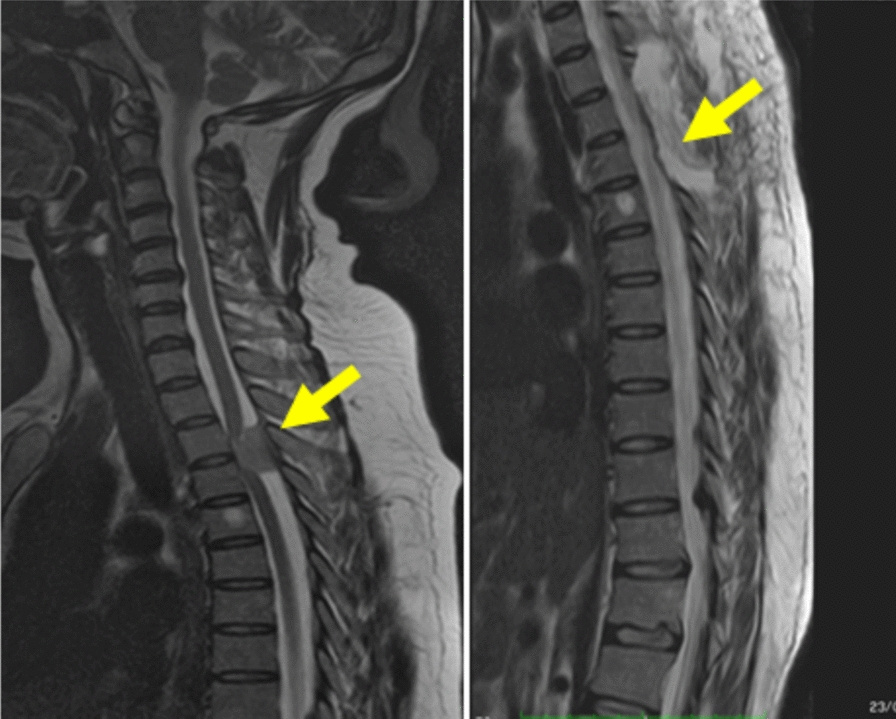

Remote intracranial hemorrhage after supratentorial and spinal surgery: a three case series and review of literature